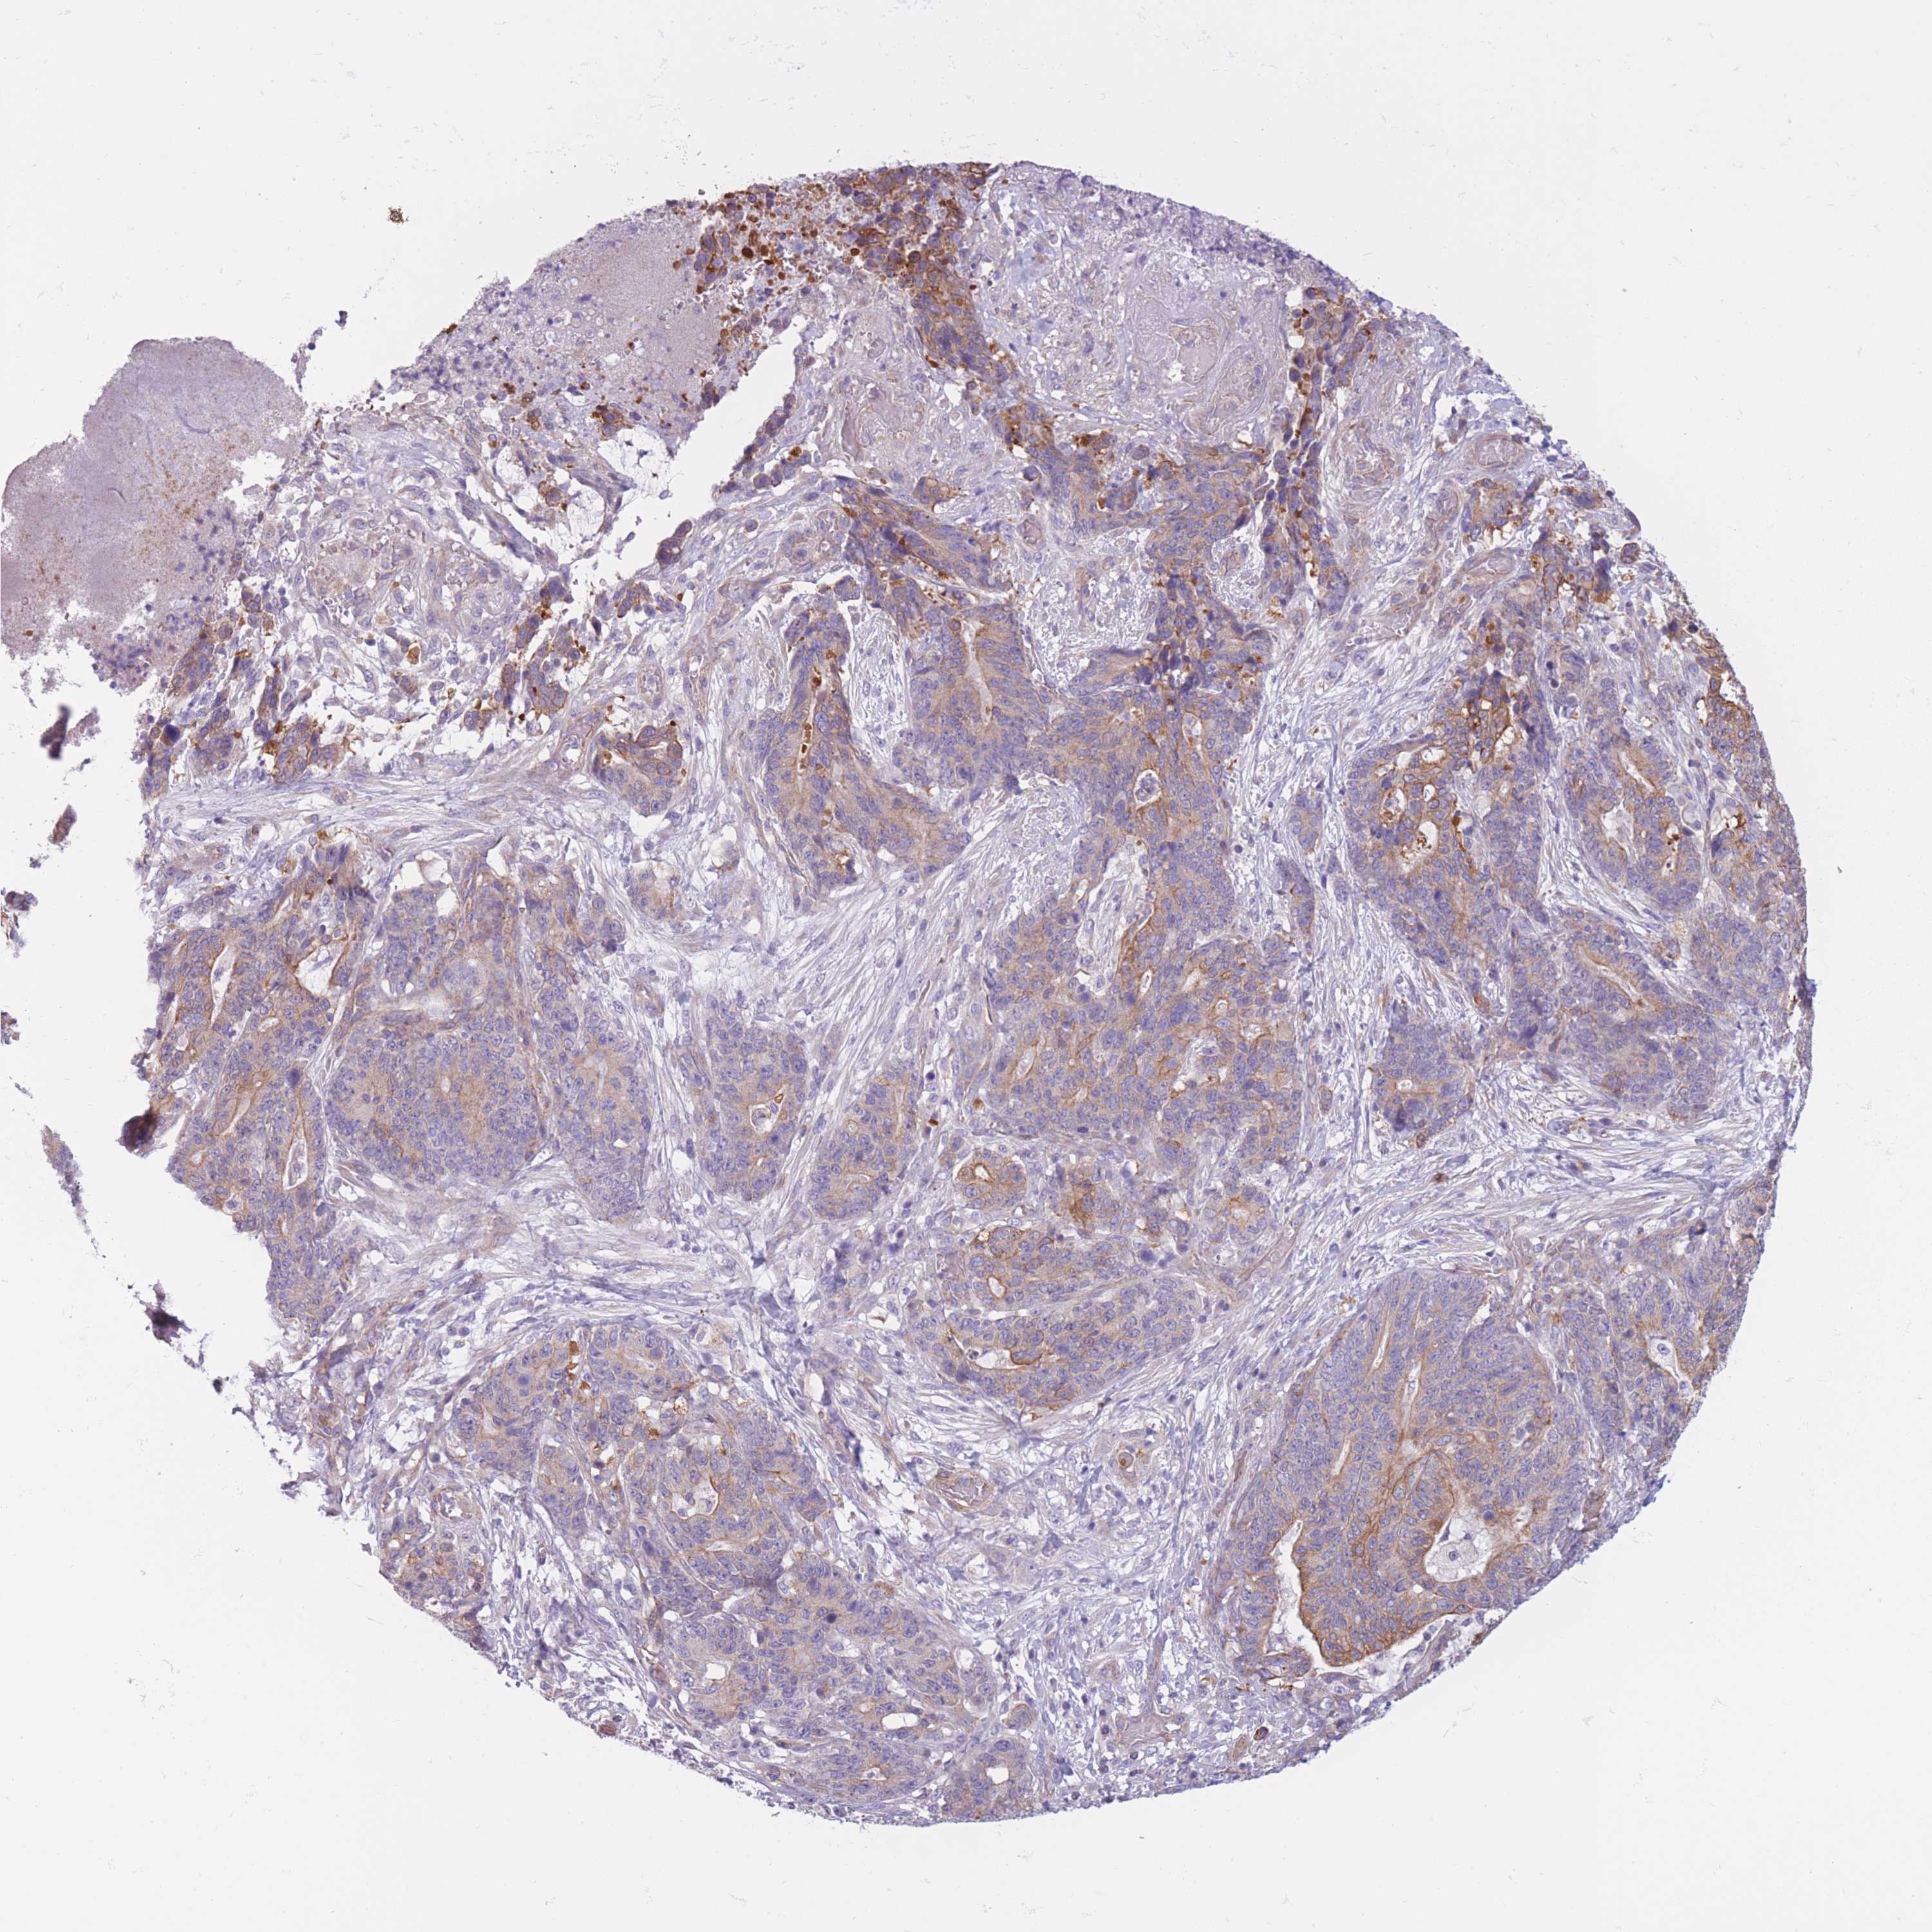

STOMACH CANCER - Protein expressioni

A mouse-over function shows sample information and annotation data. Click on an image to view it in a full screen mode. Samples can be filtered based on level of antibody staining by selecting one or several of the following categories: high, medium, low and not detected. The assay and annotation is described here.

Note that samples used for immunohistochemistry by the Human Protein Atlas do not correspond to samples in the TCGA dataset.

Antibody stainingi

Antibody staining in the annotated cell types in the current human tissue is reported as not detected, low, medium, or high, based on conventional immunohistochemistry profiling in selected tissues. This score is based on the combination of the staining intensity and fraction of stained cells.

Each image is clickable and will lead to virtual microscopy that enables deeper exploration of all samples and also displays staining intensity scores, fraction scores and subcellular localization as well as patient and tissue information for each sample.

Antibody CAB080099

Staining

High

Medium

Low

Not detected

Intensity

Strong

Moderate

Weak

Negative

Quantity

>75%

75%-25%

<25%

None

Location

Nuclear

Cytoplasmic/membranous

Cytoplasmic/membranous,nuclear

Adenocarcinoma, NOS

Adenocarcinoma, High grade